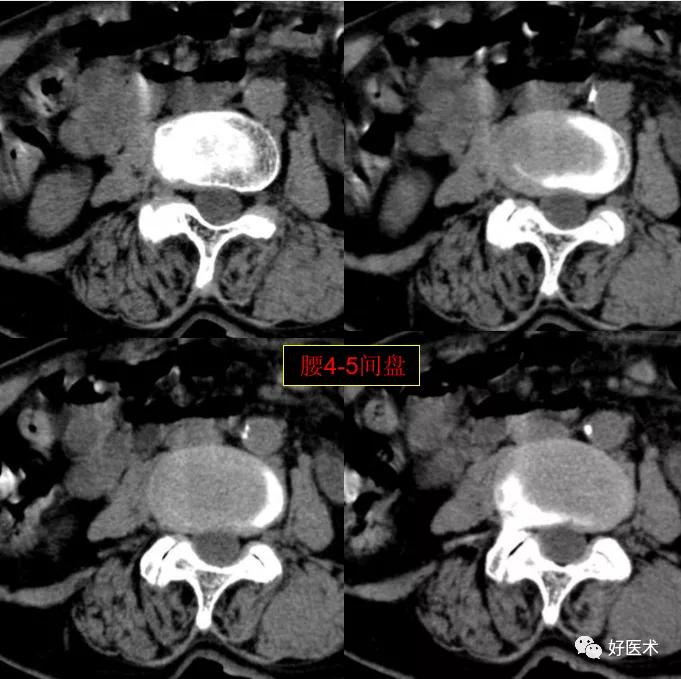

腰4-5间盘膨隆, 双侧椎小关节积气

发现了什么?左侧竖脊肌较右侧明显肿胀饱满, 肌间脂肪间隙消失!!